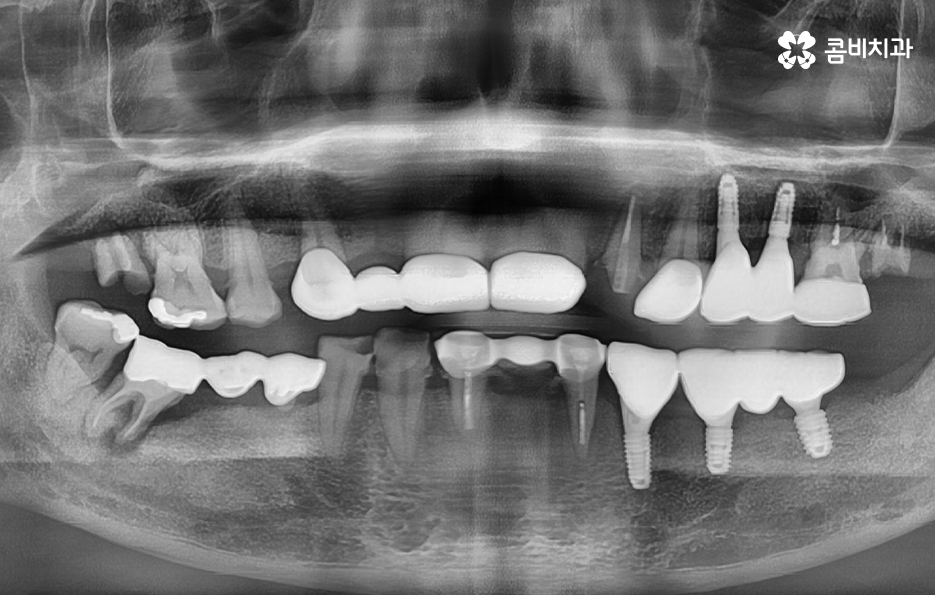

위 사진을 보시면 치아를 이미 잃은지 시간이 지난 상태의 치조골 즉 잇몸 뼈의 상태인 부위도 있고 어떤 치아는 거의 뿌리 부분만 남아 있으며 어떤 치아는 여러개의 보철물이 이어져 있는 상태인 경우도 있는데요

엑스레이 상태만 봐도 치아 저작 기능이 상당히 저하되어 있고 치아 상태가 매우 좋지 않음을 느낄 수 있을 정도인데 사실 임플란트를 필요로 하는 환자분들의 상당 수는 50대 이후부터 노년기에 치아 상실로 인한 임플란트의 필요성을 절실하게 느끼시는 분들이 많고 이미 여러 이유들로 인해 치아도 많이 발치된 경우도 있고 발치를 해야할 상황에서 임플란트를 알아보시는 분들이 많이 있어요

물론 30대 이전에도 치아를 잃게 되시는 분들도 많지만 일반적으로 40,50대 이전에는 충치나 사고로 인해 치아 하나 정도를 잃고 임플란트를 알아보시는 분들이 많고 잇몸이나 전신건강의 상태가 양호하신 분들이 많지만 50대 이후 특히 60대 이후에는 이미 치아를 잃고 시간이 지난 후에 임플란트를 하시는 분들과 치주염으로 인해 여러 치아를 잃게 되는 경우가 많기 때문에 위 엑스레이의 상태처럼 치아 뿐 아니라 잇몸 상태가 이미 안좋은 분들은 흔한 사례라고 할 수 있어요